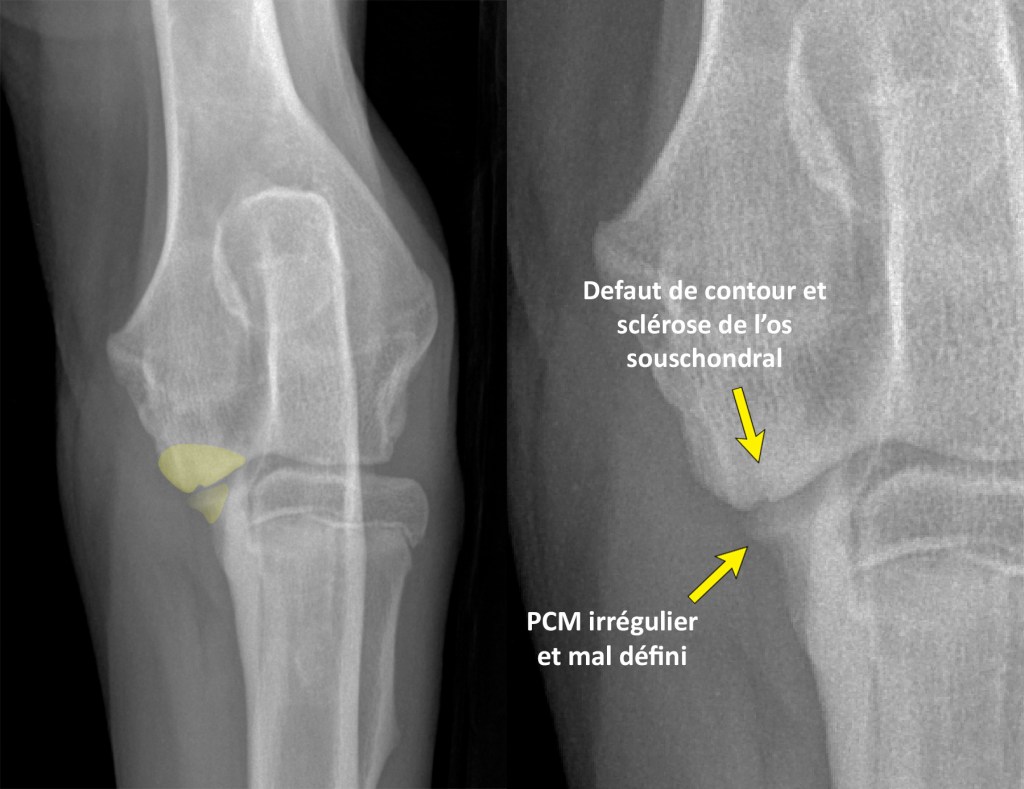

CrCd-annotee